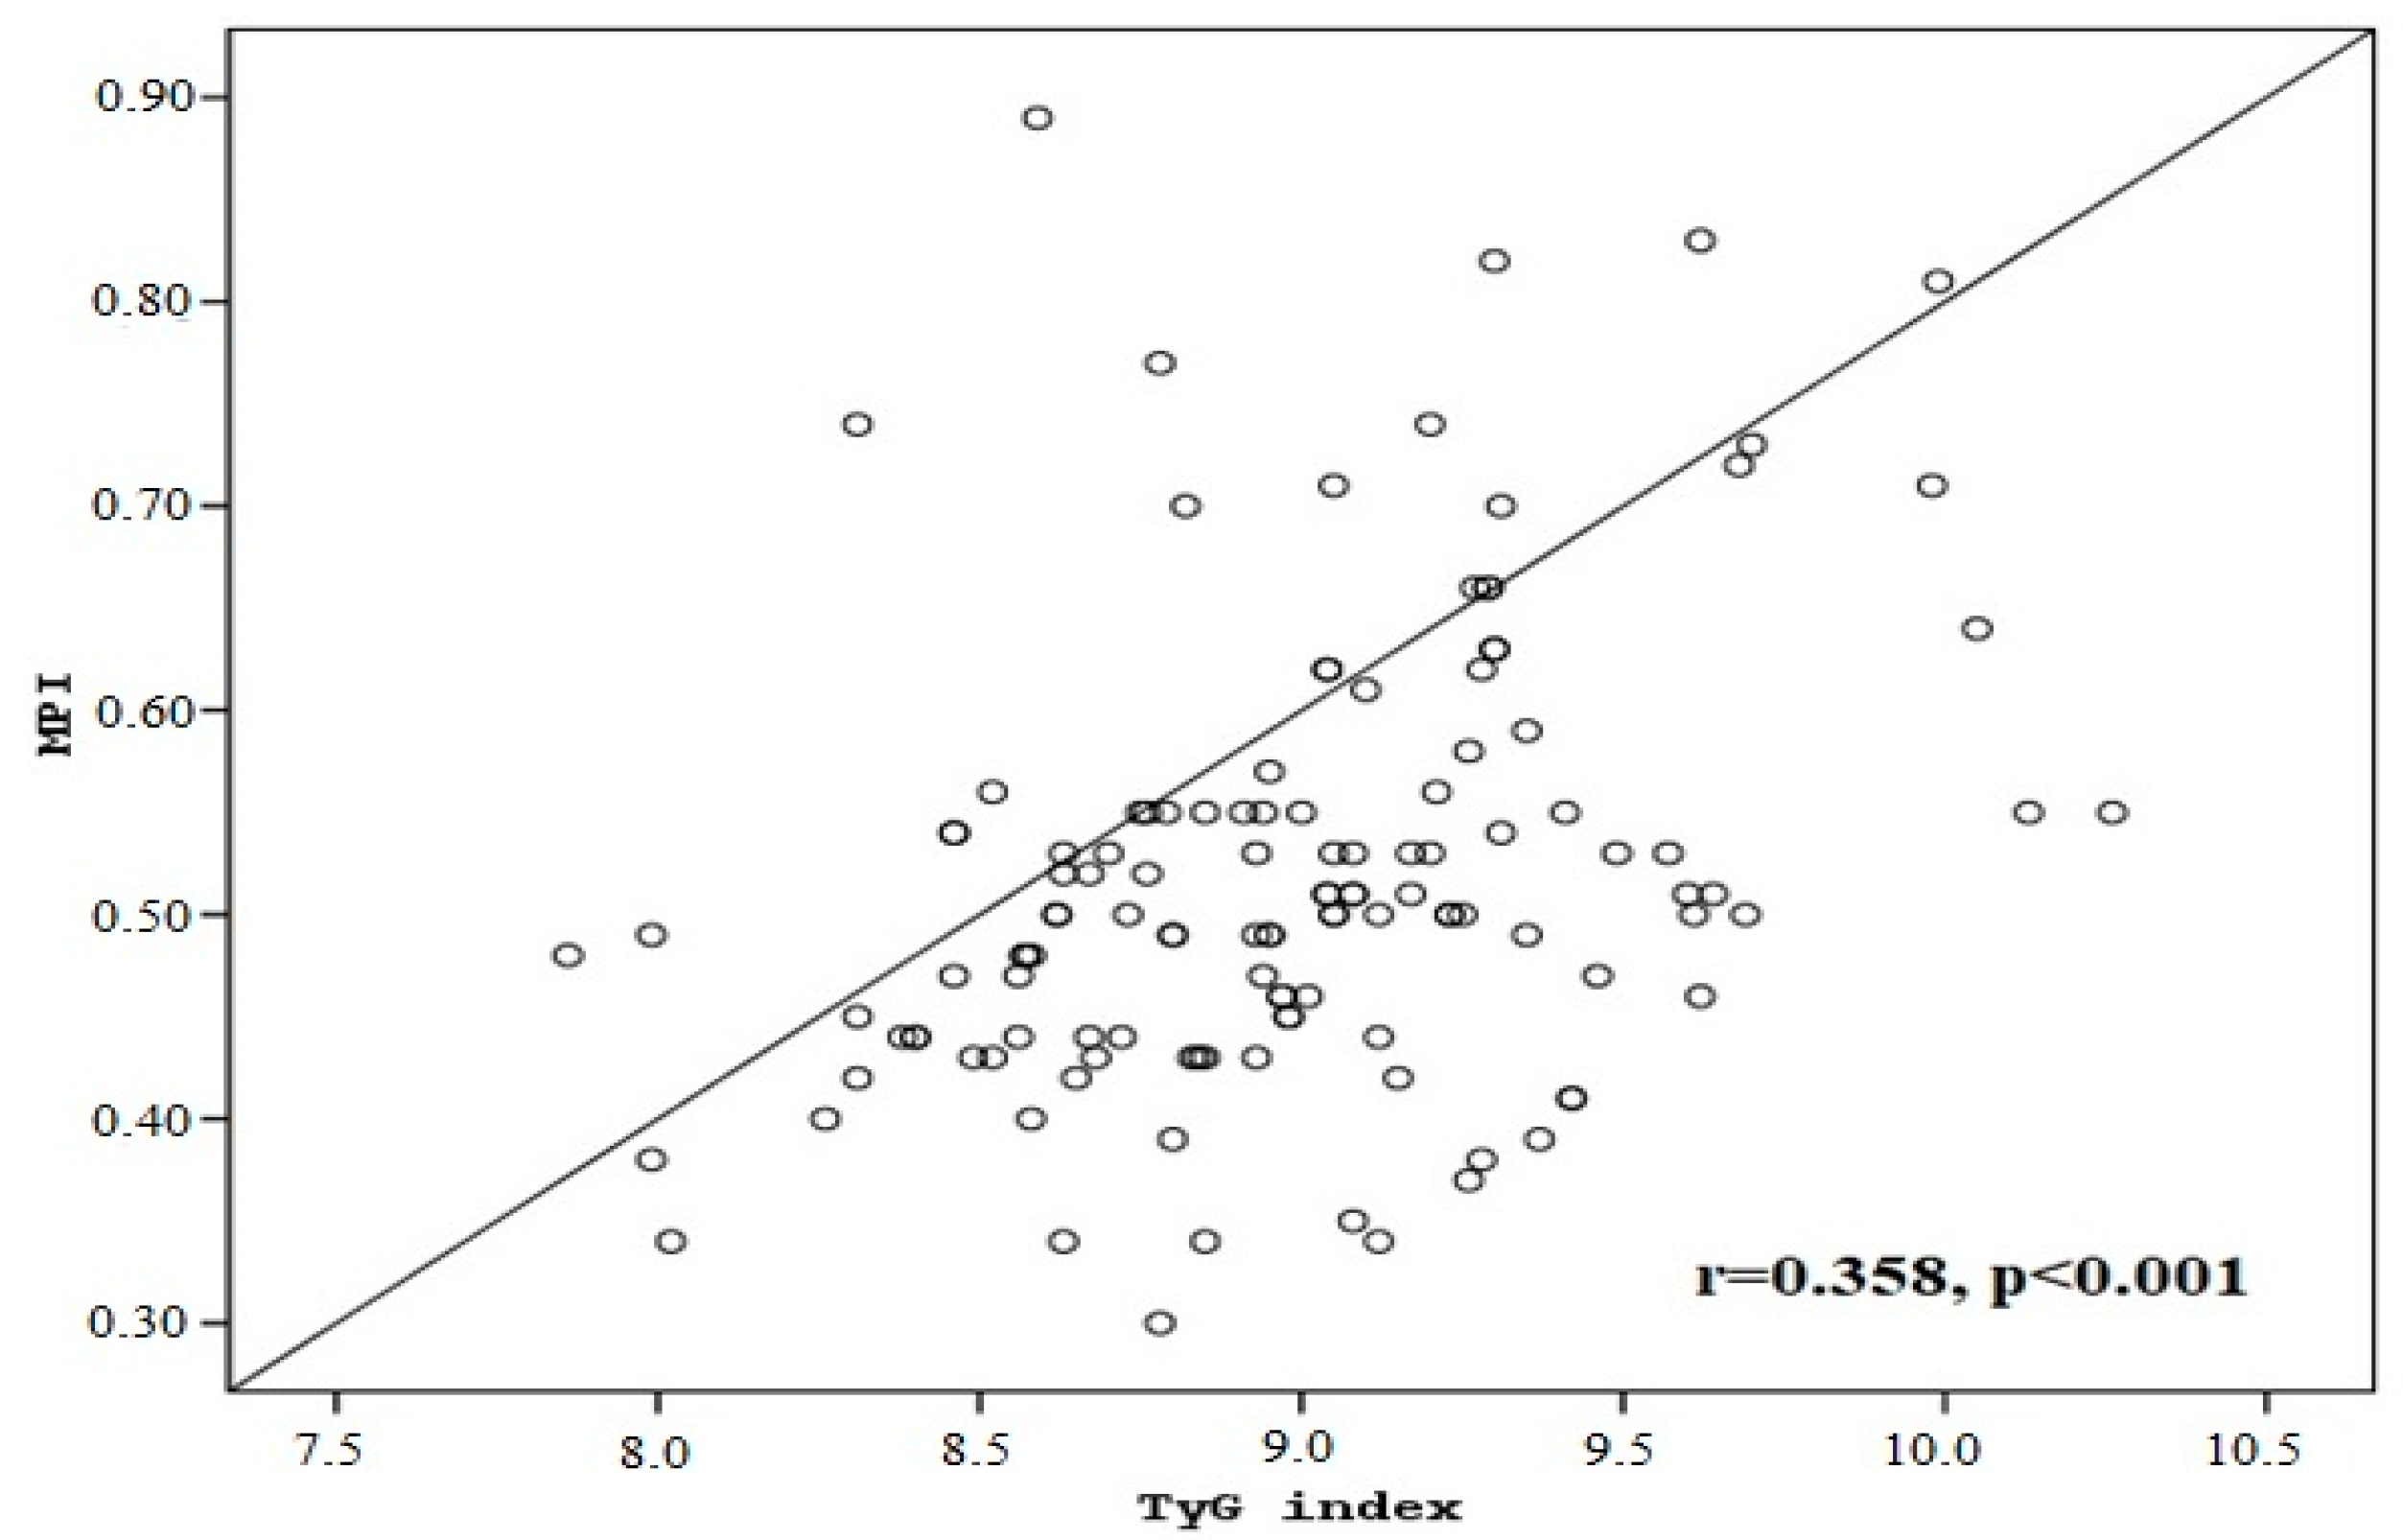

3. Results

4. Discussion

4.1. Novelty and Clinical Implications